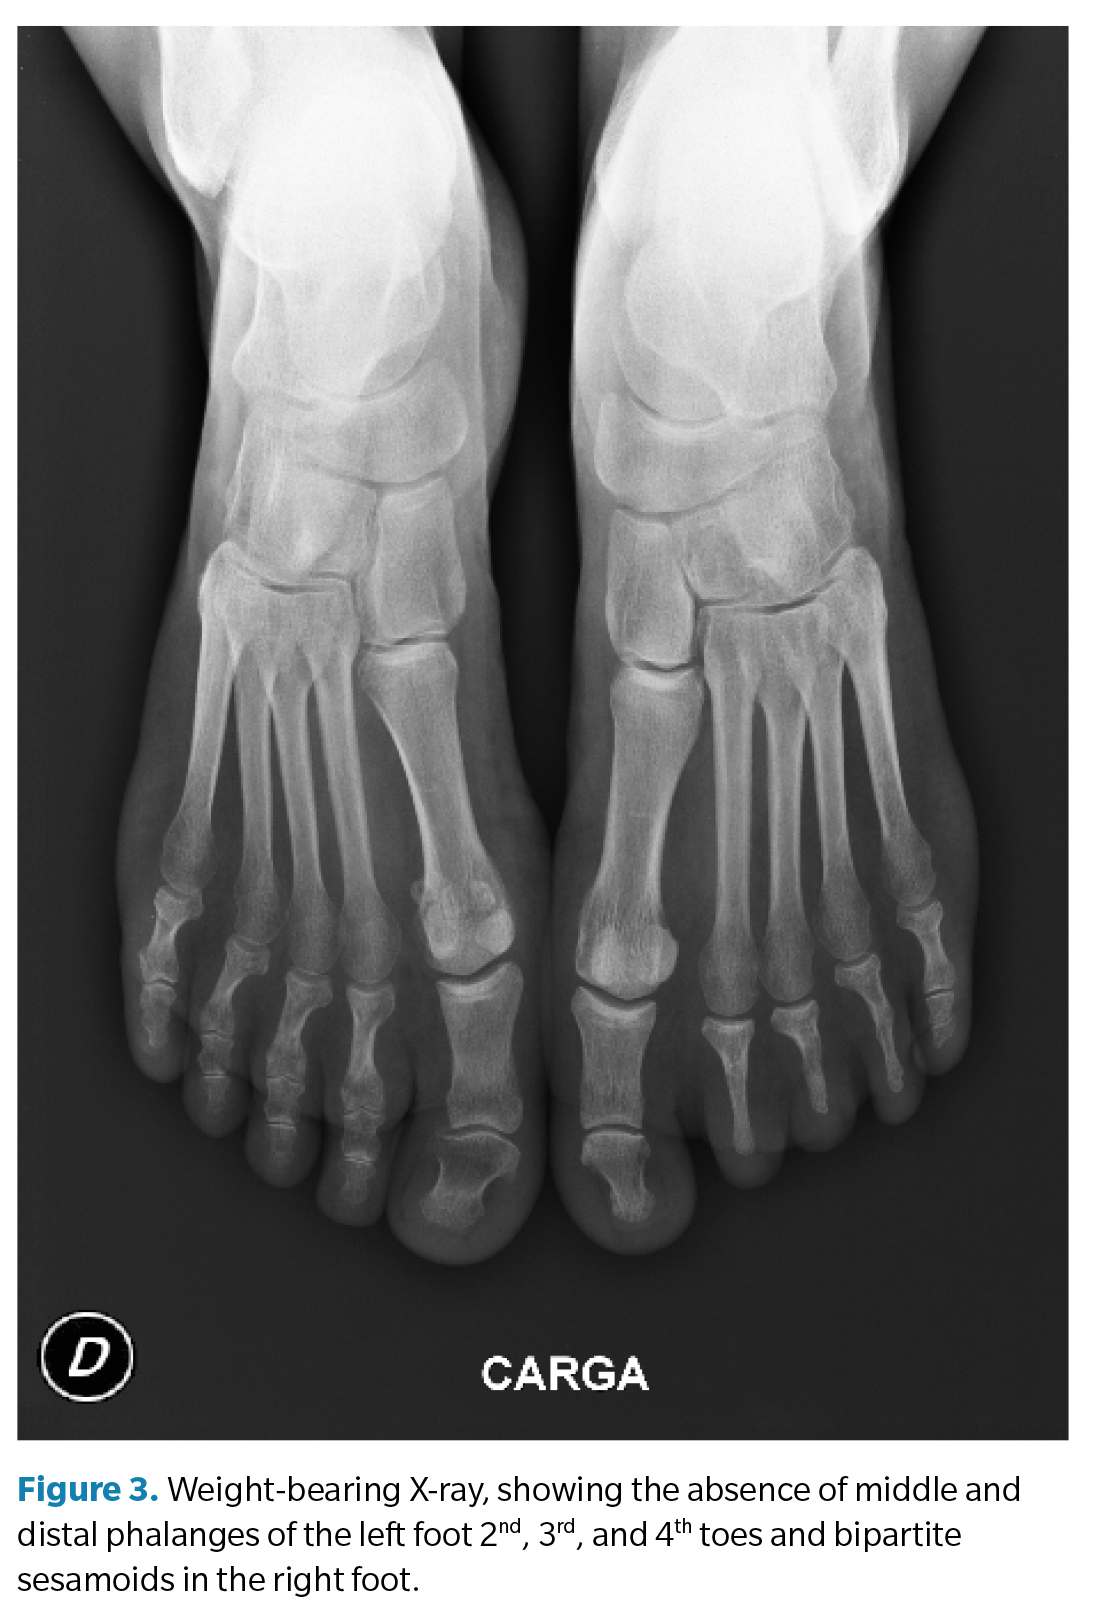

Subsequently, a weight-bearing X-ray was performed in the anteroposterior projection to complement the examination. Exceptionally, the absence of middle and distal phalanges of the 2nd, 3rd, and 4th toes of the left foot was found (Figures 2 and 3). A difference in the metatarsal formula was observed between both feet, showing a minus index in the left foot and a plus-minus index in the right one. Findings were consistent with isolated BBD.

The prevalence of DBD is extremely rare and may occur as an isolated trait or as part of a complex malformation of a syndrome(14). The phenotypes of DBD include facial defects and deformities of the fingers, including the nails, all of which are part of a syndrome. In this case report, the patient presented unilateral DBD with involvement of the 2nd, 3rd, and 4th middle and distal phalanges. The review article by Temany et al. indicated that surgery is only recommended if BD affects the function of the limb or for aesthetic reasons, but it is generally not necessary(9). In our case report, no plantar keratosis was observed, which would suggest a biomechanical alteration, with a different metatarsal formula in each foot.